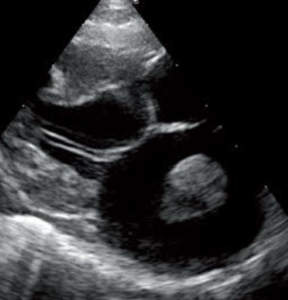

肥大型心筋症(HCM)が進行した猫の心エコー(超音波検査)画像。著しく拡大した左心房内に、巨大な血栓(白く丸い塊)が形成されている様子が鮮明に確認できます。この血栓が大動脈に流出すると、後ろ足の麻痺や激痛を伴う致死的な猫大動脈血栓塞栓症(FATE)を引き起こす極めて危険な状態を示しています。

【心エコー検査像】猫の肥大型心筋症:拡大した左心房内に形成された巨大な血栓(白い塊)。これが血流に乗って流れると、非常に危険な血栓症を引き起こします。